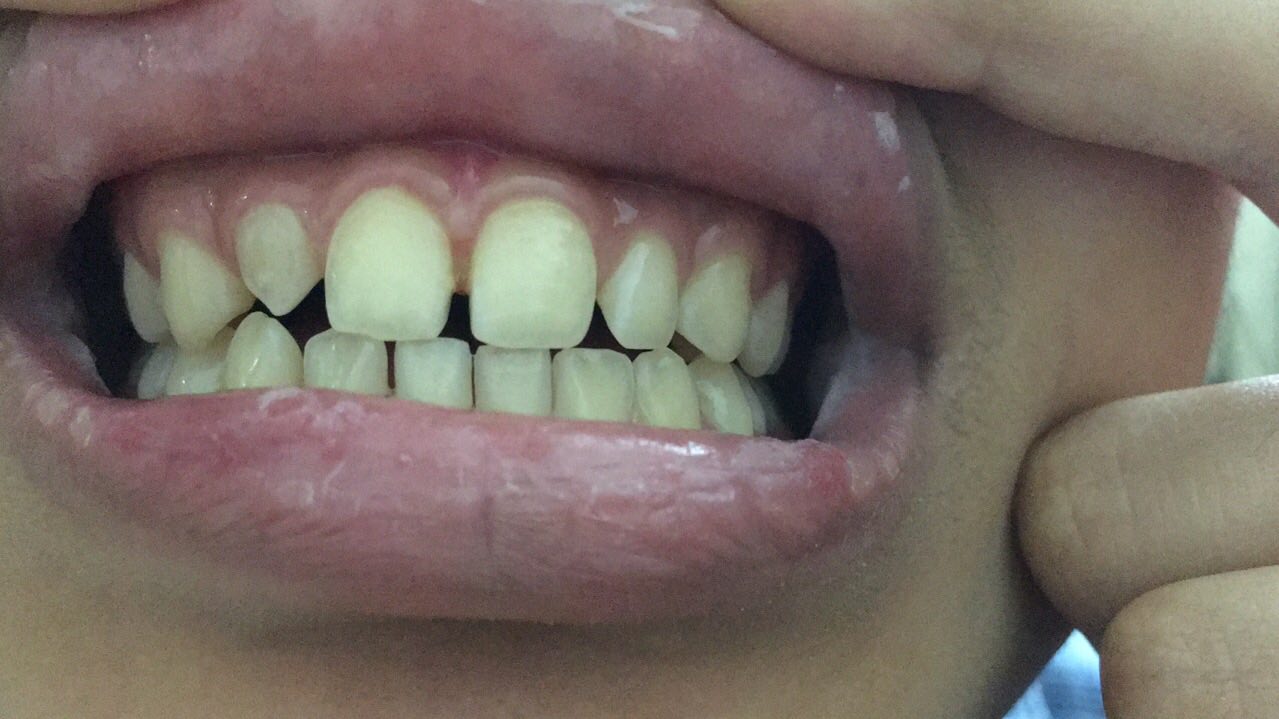

• Răng sứ thẩm mỹ

Bác sĩ Nguyễn Văn Hoàng Minh là người sáng lập ra Nha khoa Minh Nguyên. Là thành viên hiệp hội Implant thế giới ICOI (International Congress of Oral Implantologists thành lập từ năm 1972 tại Hoa Kì), Bác sĩ Nguyễn Văn Hoàng Minh đã tu nghiệp các nước Mỹ, Pháp, Đức,Thụy Sĩ, Hàn Quốc… và có hơn 25 năm kinh nghiệm chuyên cấy ghép Implant và chỉnh hình răng thẩm mỹ.